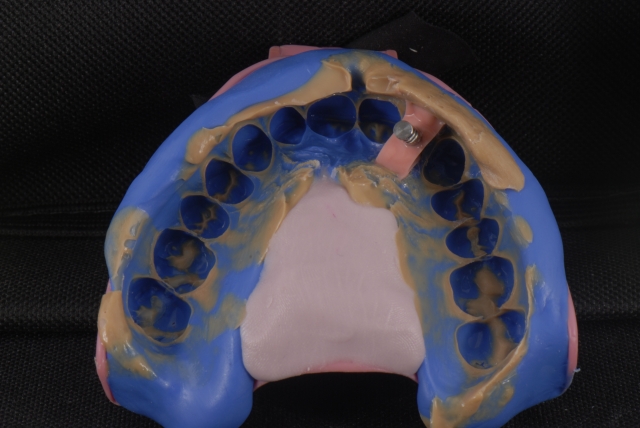

Single-tooth implants in the esthetic zone usually require a provisional restoration. The fabrication of a single-tooth implant-supported restoration requires a careful step-by-step approach to deliver a restoration that will assist the process of soft-tissue sculpting.

Here is a multi-step process showing the fabrication sequence of a screw-retained single-tooth implant provisional restoration of a lateral incisor.